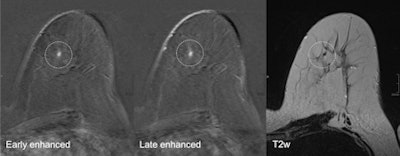

A 52-year-old patient who had breast cancer five years previously. MRI detected focus in the left craniomedial breast called BI-RADS 4, and a second opinion was requested. All images courtesy of Dr. Pascal Baltzer."Breast MRI is technically demanding, requiring excellent fat saturation, high spatial resolution, and rapid performance of postcontrast sequences," she said. "Common causes of false-positive diagnoses are represented by artifacts that can be related to the patient or to technical parameters."

Second-look ultrasound of the lesion. It's an oval, horizontally oriented lesion with circumscribed borders, posterior acoustic enhancement, and no hypervascularization. Internal features unspecific hypoisoechoic. It was found to be probably benign on ultrasound, and followed up over two years without evidence of growth."We all do a lot of examinations; most of them we do not immediately get feedback from," he said. "I heard doctors from the German screening program brag, calling their sensitivity 100% -- that is of course they see the cancers they detect, not the ones they miss. Regarding second-look ultrasound, it is similar and a lot of things can be taught: How often do I find a correlate for MRI lesions? Can I also see nonmass lesions? Can I upgrade or downgrade lesions using ultrasound? What lesions am I likely to miss and can I do anything about it?"